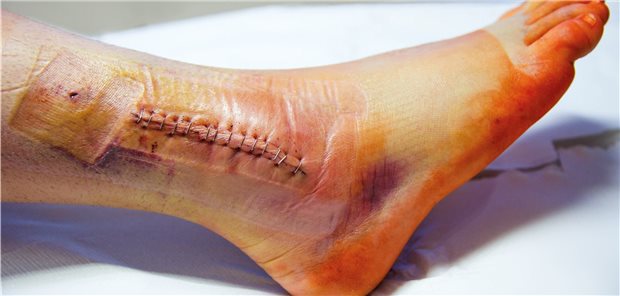

Auf Basis von schwacher Evidenz gibt es einem IQWiG-Bericht zufolge nur einen Anhaltspunkt dafür, dass sich nach Op und Training mit aktiver Bewegungsschiene die Beschwerden am Fuß mindern lassen.